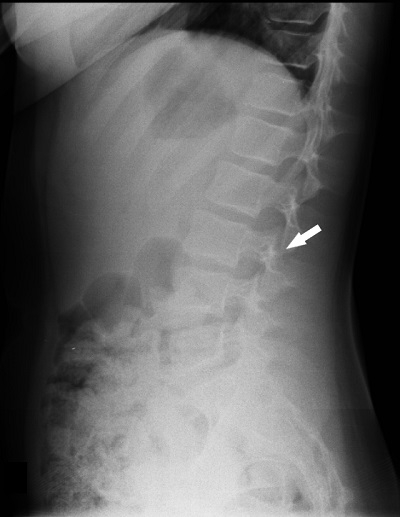

Ante una dorsalgia con datos de alarma (afectación neurológica) se realiza radiografía de columna vertebral (Fig. 1) que muestra una lesión lítica, expansiva, en pedículo derecho a nivel T10 y resonancia magnética (RM) de columna vertebral donde se aprecia una masa lobulada insuflante con cortical conservada pero adelgazada y nivel líquido en su interior en elementos posteriores de T10 que se introduce hacia el cuerpo vertebral, con componente epidural derecho que ocupa el 50-75% del canal medular y compresión medular con alteración de señal por mielopatía (desde nivel T8-T9 hasta cono medular), planteando el diagnóstico diferencial con lesiones tumorales de localización vertebral posterior, como son el osteoblastoma y el quiste óseo aneurismático (Fig. 2).

| Figura 1. Radiografía anteroposterior de columna vertebral: lesión lítica en pedículo derecho de T10 (flecha) |